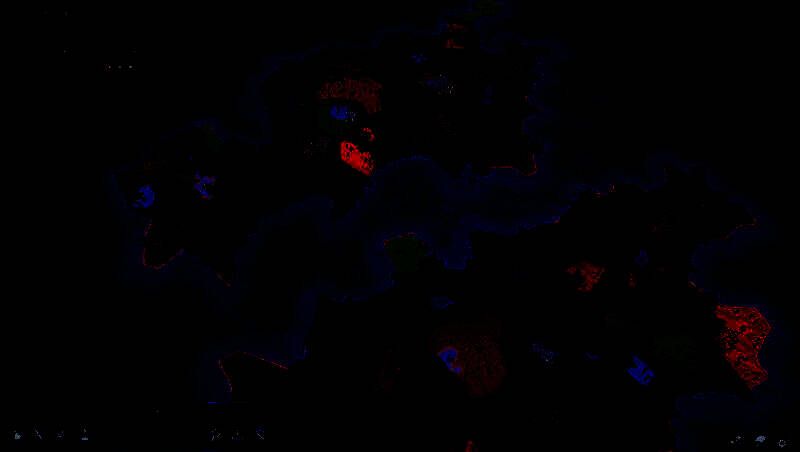

游戏采用了精致的图形风格,色彩鲜艳且丰富,为玩家呈现出一个美轮美奂的奇幻游戏世界。无论是茂密的森林、雄伟的山脉,还是繁华的城镇、神秘的地下城,都绘制得十分细腻。角色和怪物的设计各具特色,动作流畅自然。光影效果的运用也相当出色,营造出逼真的环境氛围,增强了游戏的沉浸感。同时,游戏的界面设计简洁明了,操作便捷,让玩家能够专注于游戏的创作和经营过程。